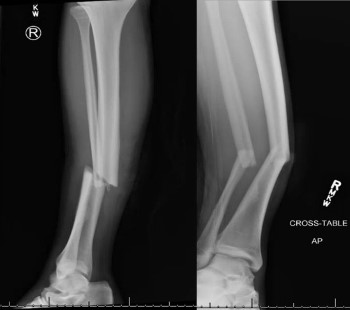

X-Ray Results

Right Tib-Fib Xray: Right angulated mid-shaft fracture of tibia and fibula